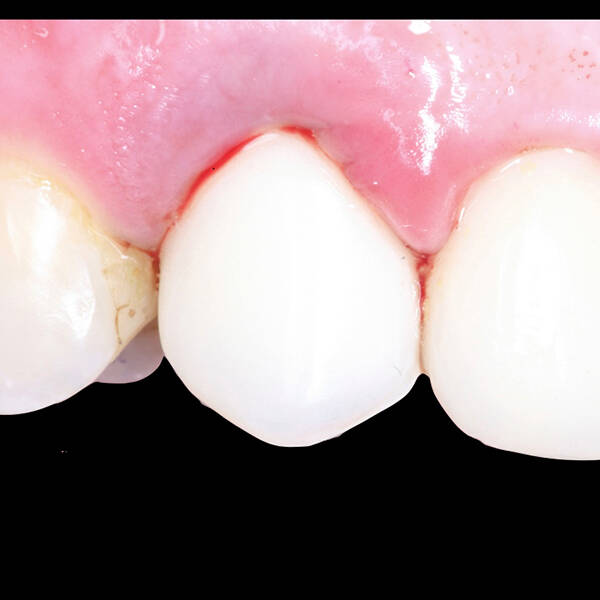

- Fixação da Prótese: Em até 72 horas após a cirurgia, a prótese provisória é instalada, permitindo que o paciente recupere a funcionalidade e a estética imediatamente.

- Conforto e Estética: A prótese provisória é funcional e visualmente semelhante aos dentes naturais.